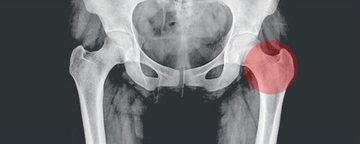

4. 근골격계 원인

골반저 기능 장애 및 근육 긴장과 같은 골반 부위와 관련된 근골격계 문제는 골반 통증을 유발할 수 있습니다. 골반저 기능 장애는 골반 장기를 지지하는 근육, 인대 및 결합 조직에 문제가 생기는 것을 말합니다.

이러한 근육이 긴장하거나 해당 부위에 부상을 입으면 골반 쪽에 지속적인 통증이 발생할 수 있습니다.